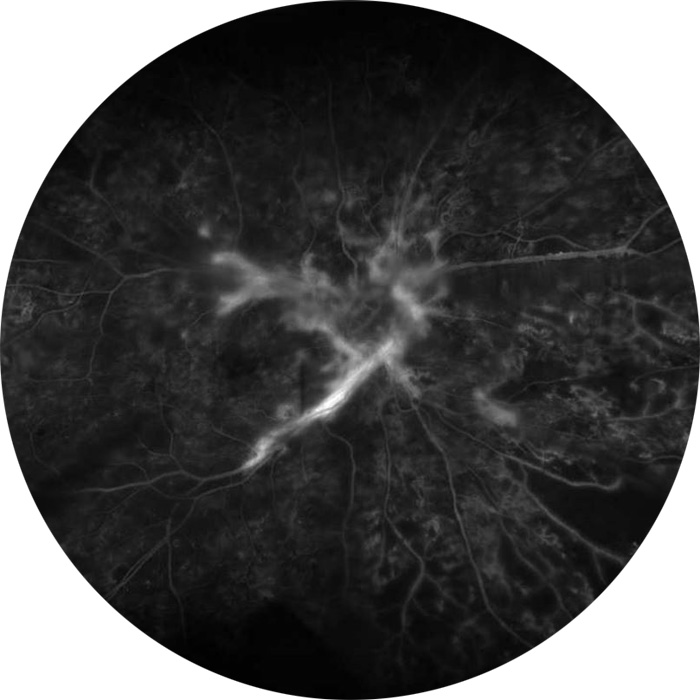

Angiographie rétinopathie diabétique proliférante

Par la réalisation d’un fond d’œil avec l’instillation préalable d’un collyre permettant la dilatation des pupilles.

Des photographies de la rétine seront systématiquement prises afin de comparer l’état de la rétine entre les différentes consultations.

Parallèlement au fond d’œil, un examen ophtalmologique complet sera réalisé afin de s’assurer de l’absence d’altération de la vue, de contrôler la pression oculaire et de compléter ou non le bilan par la réalisation d’examens complémentaires (angiographie rétinienne, tomographie à cohérence optique…).